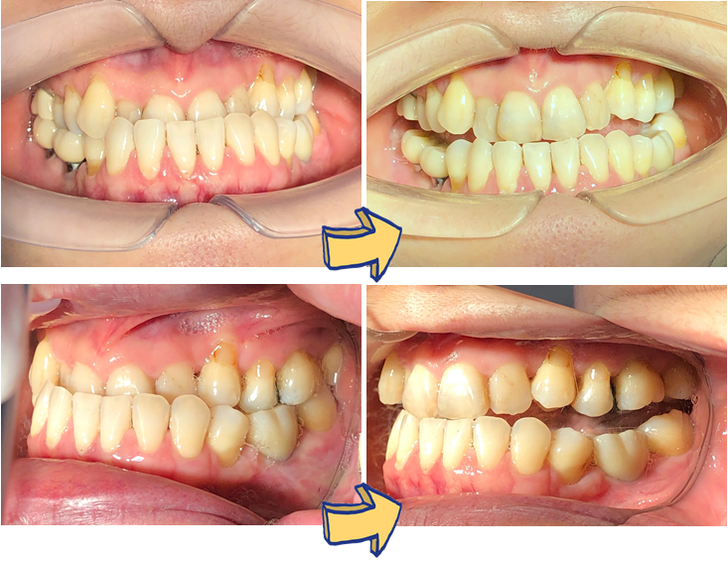

故事是這樣的,郭媽媽的女兒是讓黃汝萍醫師進行隱適美青少年矯正的,但因為疫情戴口罩的緣故,療程進行了一年,黃醫師還沒看見媽媽的廬山真面目,但郭媽媽看著孩子做隱適美牙套,輕輕鬆鬆牙齒就有了巨大的改善,終於,有一天門診中,郭媽媽鼓起勇氣,主動將口罩拿下來,問黃醫師說:她也很為牙齒困擾,年輕時問過牙醫師,牙醫師告知,她的戽斗需要開刀才能處理,想到要開刀,郭媽媽決定放棄處理,也就這樣接納了半輩子….

想不到,黃汝萍醫師請他下顎動一動,輕鬆地慢慢咬起來,看是否可以門牙咬到門牙。然後,黃醫師說〝你的戽斗是假的〞如果郭媽媽不追求一定要標準完美的齒列,用牙齒矯正治療應該不難,效果仍會很明顯。

郭媽媽在聽完黃醫師的分析後,毅然決然開始她的矯正療程,然後當然得到非常開心的結果囉!